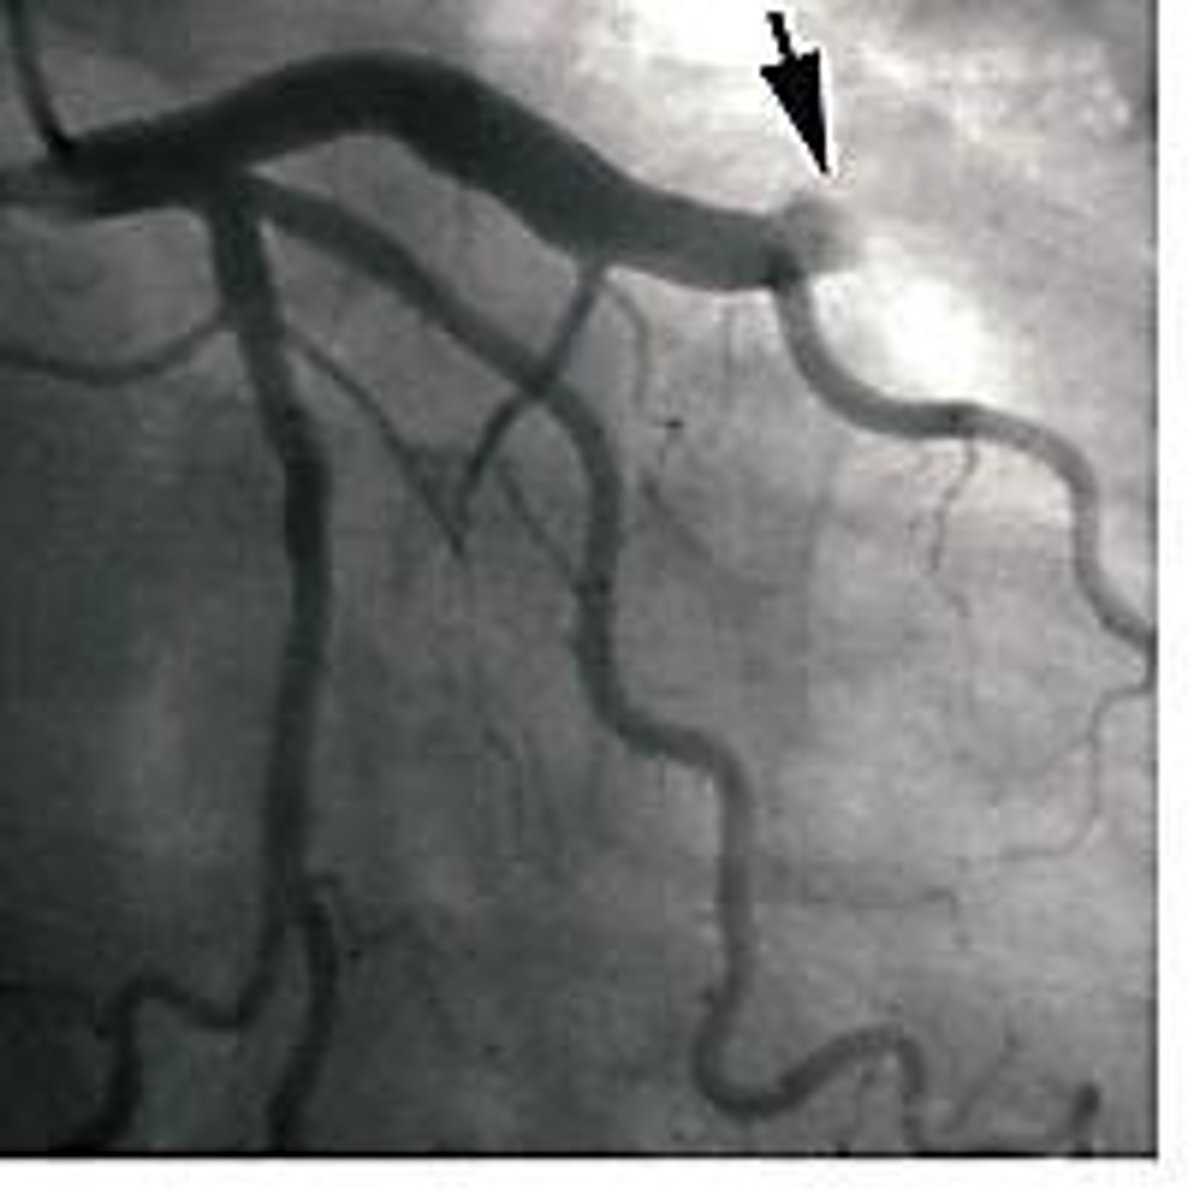

Coronary Circulation

Blood supply to heart muscle itself.

Coronary Occlusion

Blockage of coronary arteries, reducing blood flow.

<p>Blockage of coronary arteries, reducing blood flow.</p>

Atherosclerotic Plaque

Build-up in arteries, leading to occlusion.